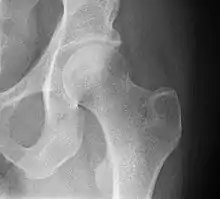

| Other names: Proximal femur fracture[1] | |

| Intertrochanteric hip fracture in a 17-year-old male | |

X-rays of the affected hip usually make the diagnosis obvious; AP (anteroposterior) and lateral views should be obtained.